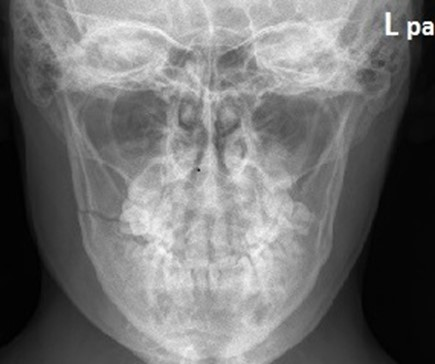

Na prawidłowo wykonanym zdjęciu zatok w projekcji PA górny zarys piramid rzutuje się

A. poniżej zatok szczękowych.

B. poniżej dolnego brzegu oczodołu.

C. powyżej zatok szczękowych.

D. na dolny brzeg oczodołu.